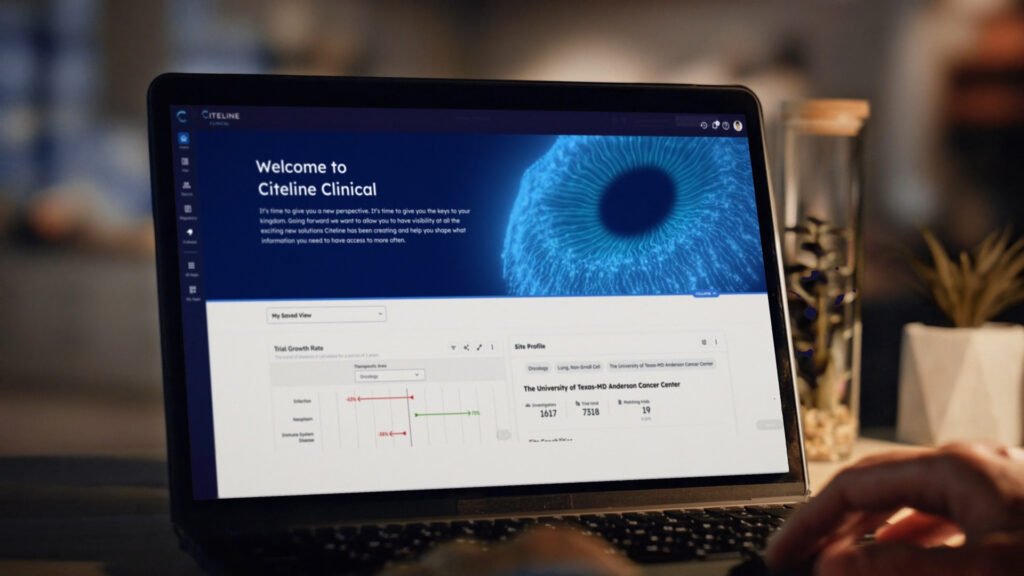

We crafted a dynamic project video for Citeline Clinical, showcasing how their AI-driven solutions are transforming clinical trials. This life-saving technology is setting a new standard in medical innovation.